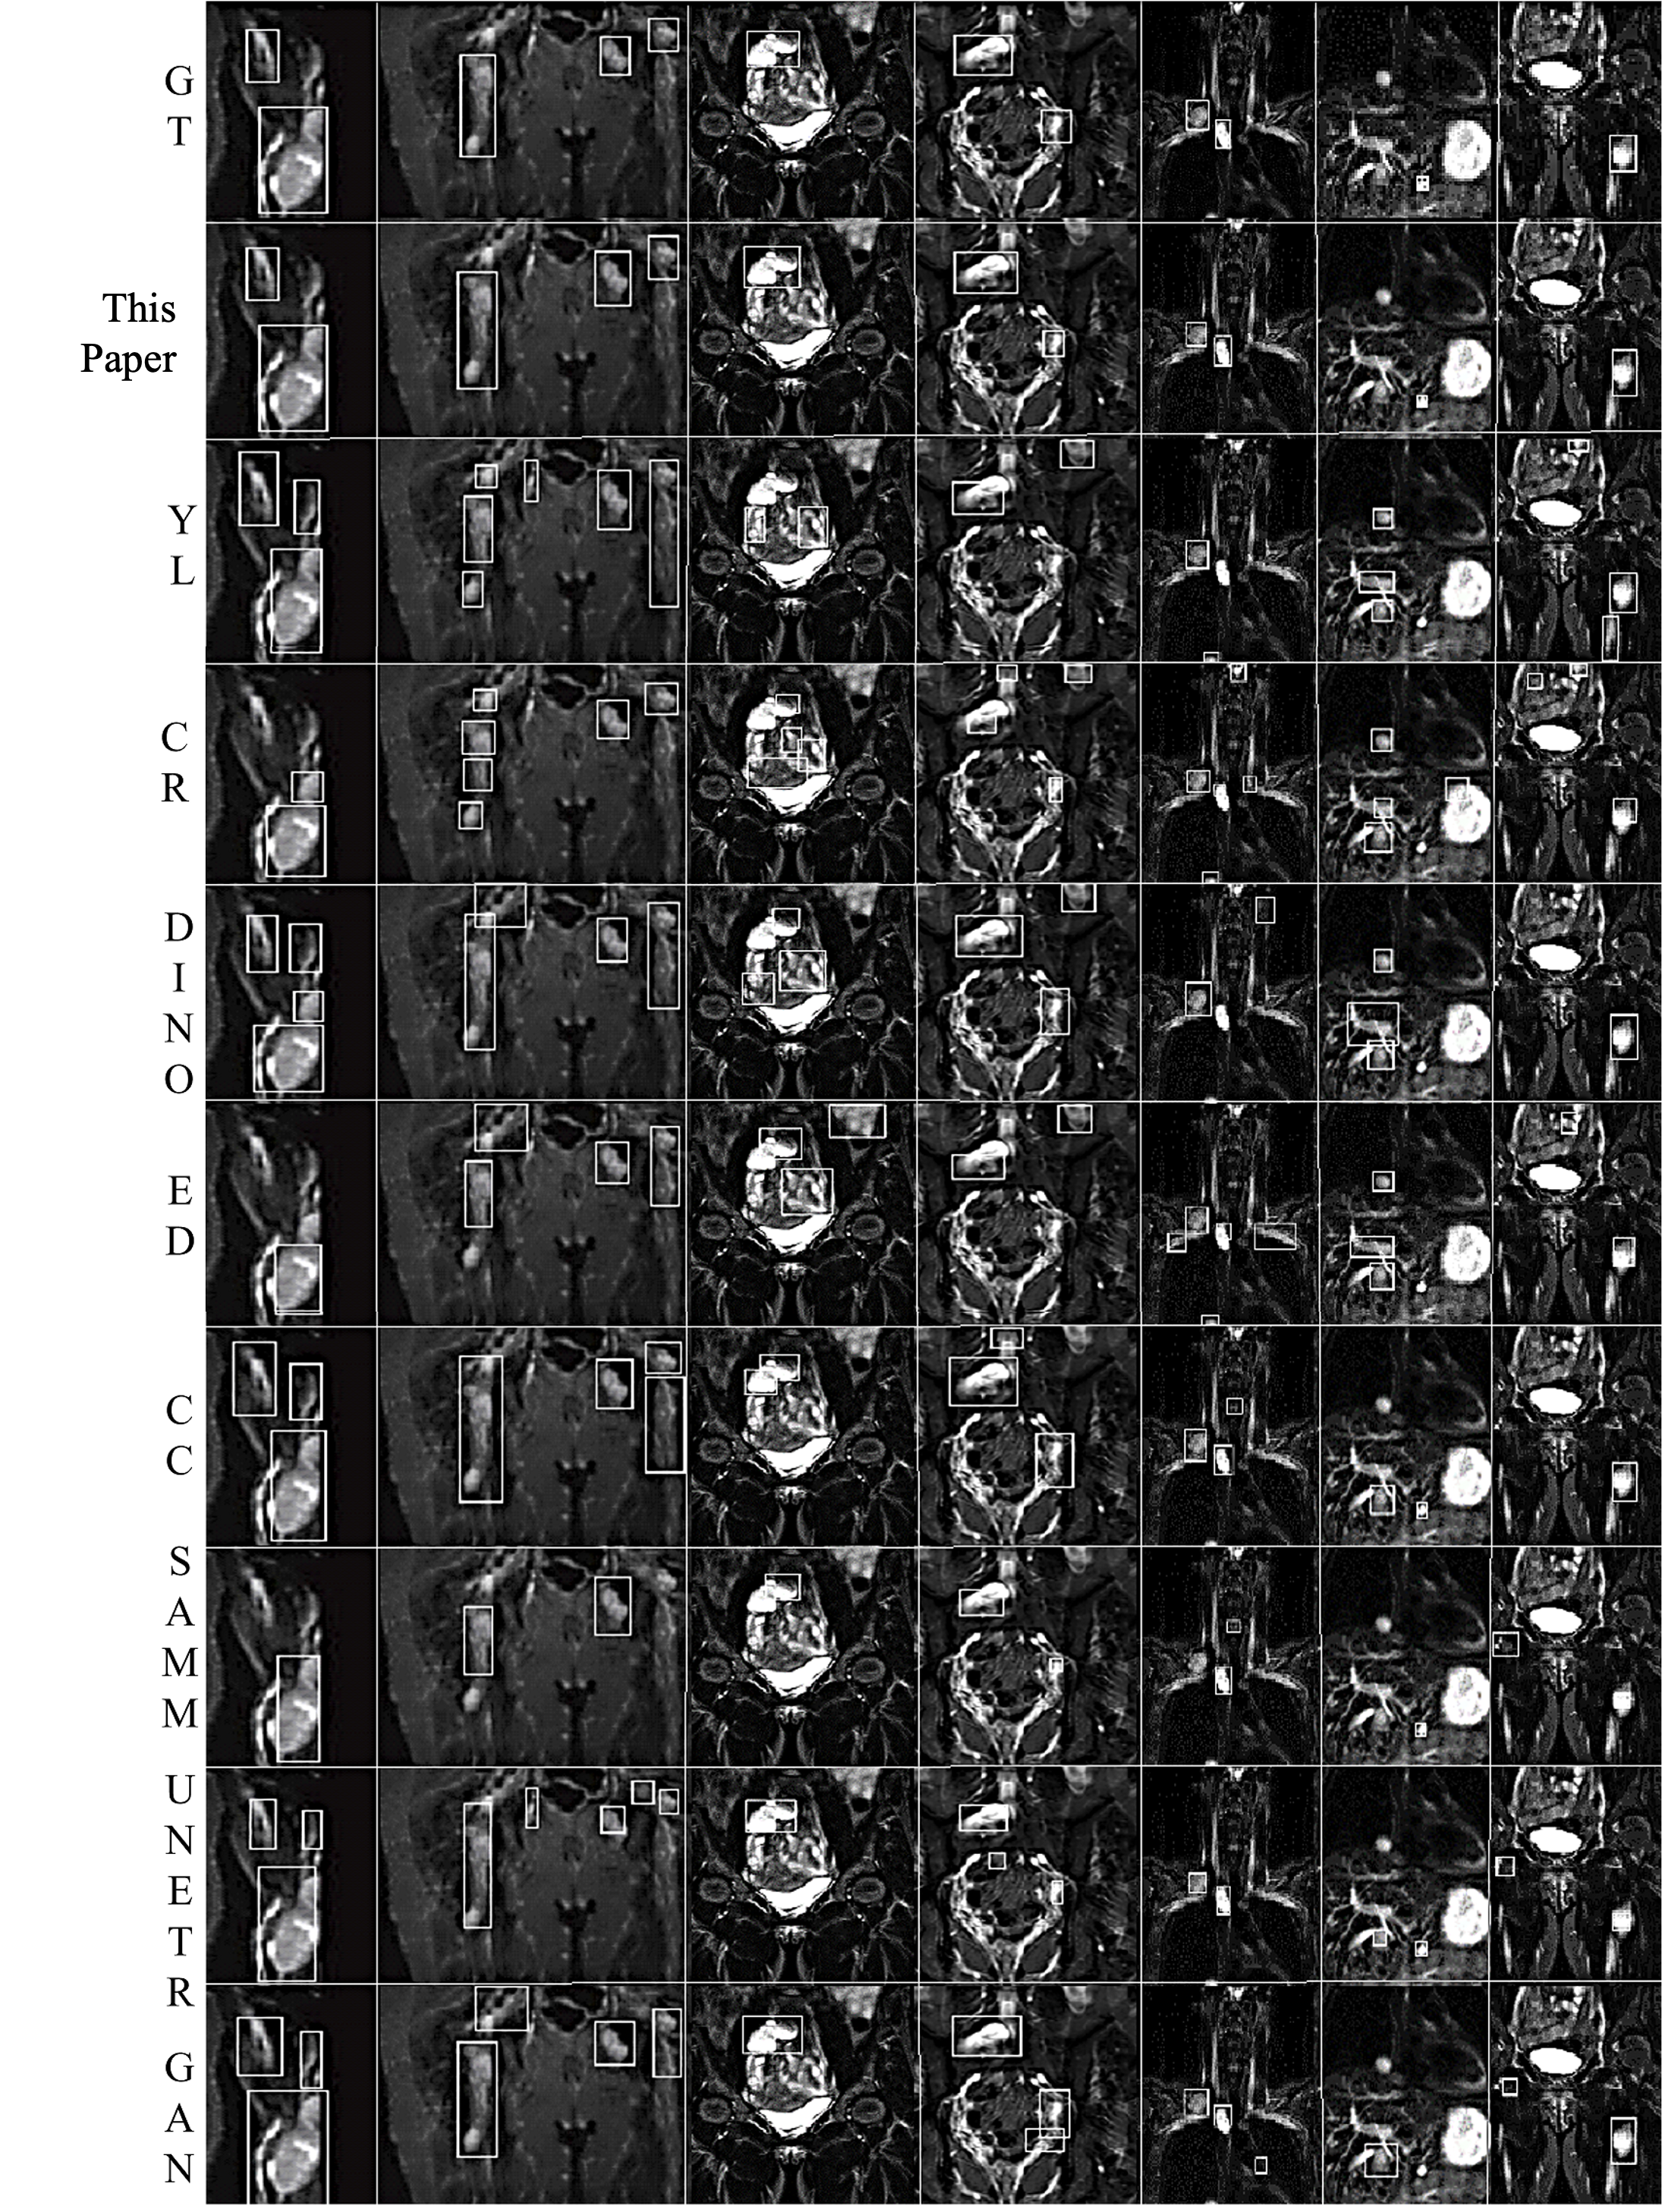

Neurofibromas may be distributed to any part of the body, mainly including the legs, arms, head and neck, chest, abdomen, and pelvis. The volume can also vary from a few cc/ml to several hundred. In the following display, 7 representative images will be selected, covering different parts of the body and volumes ranging from 5cc/ml to 500cc/ml. As shown in Figure 4, it is a comparison between the integrated learning method proposed in this paper and the detection results of 8 single-models. Here, GT, ED, YL, CR, CC, DINO, and GAN respectively represent Ground-Truth, EfficientDet-D7, YOLOv7, Cascade R-CNN, 3DConvCaps, Mask-DINO, and TransGAN. All detection results are predicted after being processed by the image enhancement algorithm proposed in this paper. From the display results, it can be seen that the detection results of the integrated learning method in this paper are basically consistent with the Ground-Truth, with only a small amount of difference near the boundary.

(1) Arm (2) Pelvis (3) Abdomen (4) Abdomen (5) Neck (6) Chest (7) Leg

Figure 4. Comparison of Detection Results by Different Methods